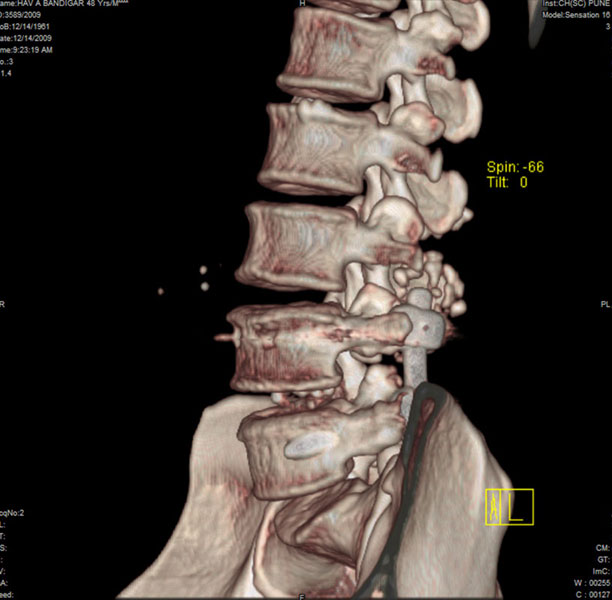

Spondylolisthesis malformations

Spondylolisthesis implies slippage of one lumbar vertebra over the next one, causing pain and nerve compression. Patient can also have difficulty in walking and numbness of the legs. Usually these patients need evaluation lumbar spine by MRI and CT scan, followed by spinal instrumentation and fusion.